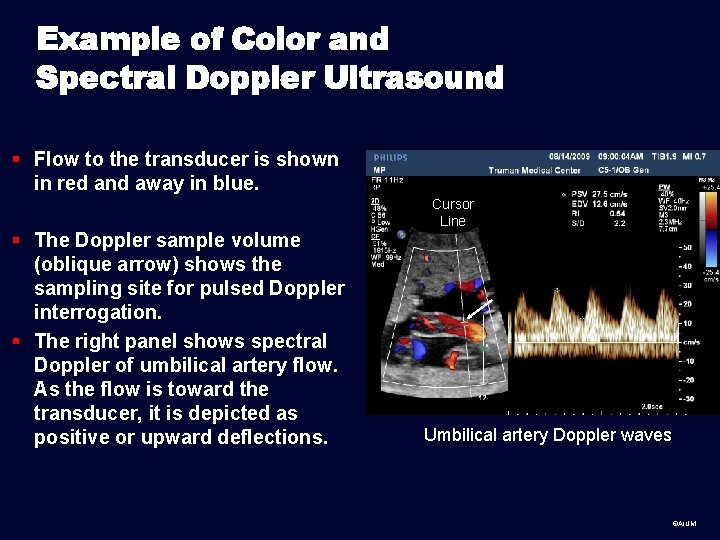

Example of Color and Spectral Doppler Ultrasound § Flow to the transducer is shown in red and away in blue. Cursor Line § The Doppler sample volume (oblique arrow) shows the sampling site for pulsed Doppler interrogation. § The right panel shows spectral Doppler of umbilical artery flow. As the flow is toward the transducer, it is depicted as positive or upward deflections. Umbilical artery Doppler waves ©AIUM